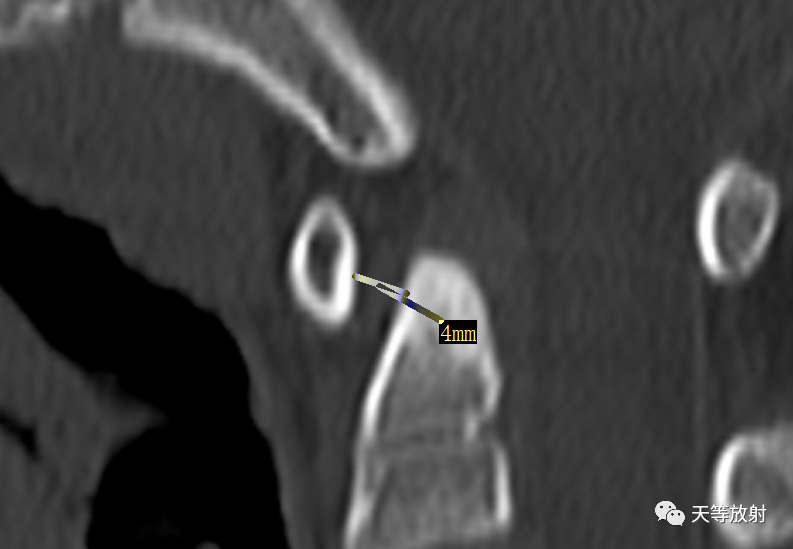

侧位环齿前间距不超过 3mm( 儿童为 4mm) ,超过即为脱位。关节呈明显“V”形变者可考虑横韧带上部撕裂; 若环齿前间距在 5-10mm,则提示其他韧带亦有损伤; 10-12mm 说明累及局部韧带。

侧位环齿间距的测量是诊断环枢椎前 -后脱位最有效和最简便的方法。

上图:侧位环齿前间距 4mm。